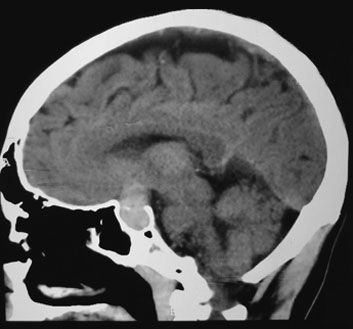

Se describe el caso clínico de un paciente masculino de 42 años de edad, sin antecedentes médicos de importancia, el cual inicia su padecimiento 13 días previos a su ingreso hospitalario con cefalea de moderada intensidad, tipo pulsátil, de predominio frontal y retroorbitario, con intensidad de 5/10 en la escala visual análoga del dolor, así como ambliopía bilateral de predominio izquierdo y fotofobia. Acude a hospital oftalmológico en donde se le realiza diagnóstico de coroidopatía serosa, sin instaurar tratamiento alguno. El cuadro clínico evoluciona continuando con cefalea, la cual aumenta de intensidad, por lo que acude con facultativo, quien recomienda realización de tomografía, en la cual se evidencia una masa hiperdensa de 2.5 x 2 cm, aproximadamente, que ocupa toda la región selar (figura 1).

La historia natural de la enfermedad en el caso clínico presentado fue secuencialmente típica a lo reportado en la literatura, siendo los síntomas más comunes cefalea, náuseas, vómitos, deterioro de la agudeza visual, oftalmoparesia, hipopituitarismo, mareos, confusión e, incluso, coma.13 El paciente presentó la tríada característica de esta entidad23 y los hallazgos tomográficos característicos de macroadenoma hipofisario; sin embargo, el diagnóstico de apoplejía pituitaria fue discretamente retardado. Un diagnóstico clínico e instrumental completo requiere una neuroimagen adecuada, un examen oftalmológico completo y un panel hormonal completo; las imágenes de tomografía computarizada (TC) pueden resaltar una apoplejía hipofisaria solo en el 25-28% de los casos. Es bien sabido que el adenoma hipofisario, que es isodenso al parénquima cerebral, es difícil de diagnosticar en la TC, incluso en caso de hemorragia. La resonancia magnética cerebral es más sensible y permite el reconocimiento de apoplejía hipofisaria en casi el 100% de los pacientes. En el caso de sospecha diagnóstica de apoplejía hipofisaria se debe preferir la resonancia magnética nuclear,13 en la cual se pueden llegar a evidenciar imágenes con forma de "figura de ocho" o "apariencia de muñeco de nieve", ya que la dureza del diafragma de la silla turca crea en el tumor un istmo.24